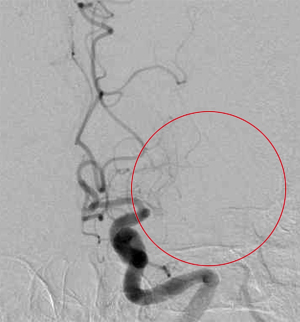

中大脳動脈が閉塞し片麻痺出現

Penumbraを用い再開通すると症状が消失した